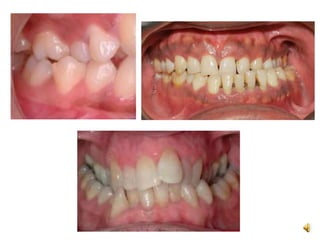

Crossbite

• It is a condition in which one or more teeth abnormally

malposed buccaly or lingually or labially with reference to

opposing teeth.

Open bite

• It is the failure of a tooth or teeth to meet their antagonist in

the opposite arch.

• It creats

– Difficulty in speech

– TMJ disorder

– Functional imbalance

– Bad aesthetics

Crossbite • It isa condition in which one or more teeth abnormally malposed buccaly or lingually or labially with reference to opposing teeth.

Open bite • Itis the failure of a tooth or teeth to meet their antagonist in the opposite arch. • It creats – Difficulty in speech – TMJ disorder – Functional imbalance – Bad aesthetics